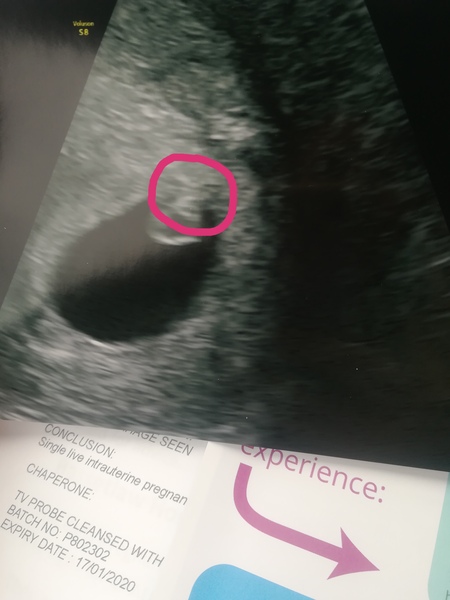

BirthdayKake · 29/11/2018 18:52

Whish, 6+3 looks a bit like this...

@Delilah7 Thank you for the ray of light and hope! So pleased for you. The other girls would never begrudge your good news, so don't even think about it being bad timing. How far along are you? I'm having a scan next week where by lmp I'll be 7 weeks exactly but by ovulation I reckon I'll only be 6w3d. Am wondering what I should be able to see at that stage.

@MakeAWhish thanks lovely. Could see a heartbeat then possibly! LMP is 8 weeks 2 days ago. So I'm measuring exactly a week behind ( late ovulation )